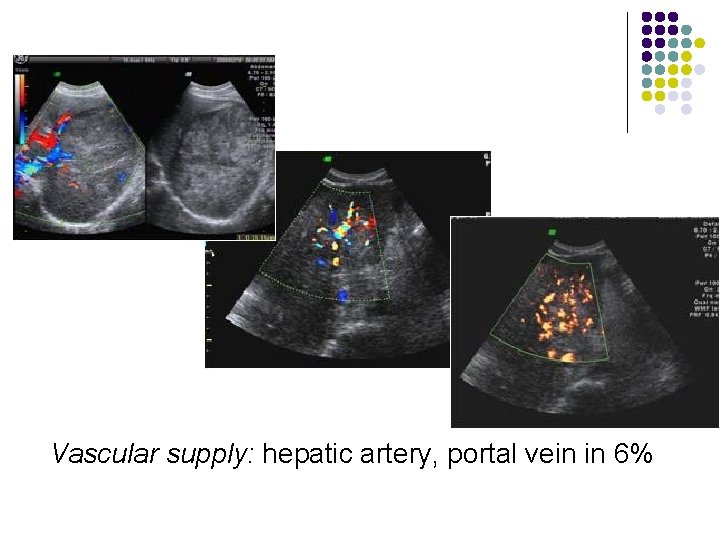

Hepatocellular Carcinoma(HCC) l Growth pattern: l solitary massive (27 -59%): l bulk in one (most often right) lobe with satellite nodules multifocal small nodular (15 -25%): l small foci of usually <2 cm (up to 5 cm) in both hepatic lobes diffuse microscopic infiltrating form (10 -26%): l tiny indistinct nodules closely resembling cirrhosis Vascular supply: hepatic artery, portal vein in 6% l l l

Vascular supply: hepatic artery, portal vein in 6%